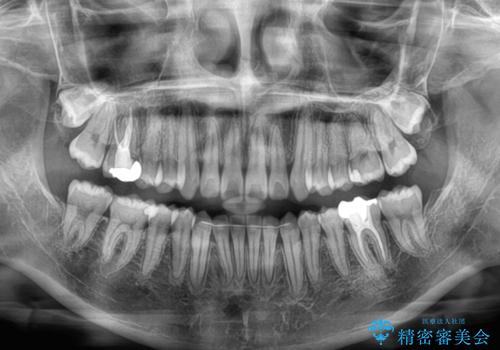

- 左右の八重歯を気にして来院された患者様です。

歯列としてはインビザラインでもワイヤー矯正でも対応できるものでしたが、インビザラインによる治療を希望されていました。

上顎の八重歯改善にインビザラインでは時間のかかってしまう可能性があり、更には口元が治療前よりも突出してしまう可能性があったため、補助装置により八重歯を事前に引き込んでおくことで、インビザラインによる治療をスムーズに行えるように計画しました。

補助装置を使用したことで、口元が突出することもなく、スムーズに仕上げることができました。